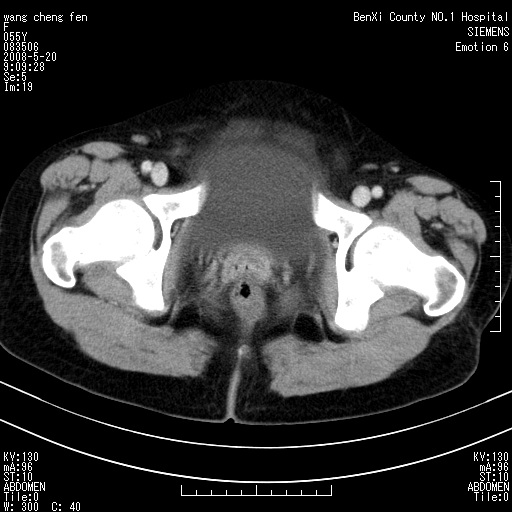

女、绝经后阴道流血3个月

左侧附件区巨大囊实性病灶,边缘光整,病灶囊壁较厚,增强示囊壁及实性部分明显强化,强化呈度与宫体实质大致相同,宫腔积液征像,未见盆腔积液等其他异常,考虑左侧卵巢囊腺癌,不除外囊腺瘤及浆膜下肌瘤坏死

左侧附件区巨大囊实性病灶,边缘光整,病灶囊壁较厚,增强示囊壁及实性部分明显强化,强化呈度与宫体实质大致相同,宫腔积液征像,未见盆腔积液等其他异常。绝经后阴道流血3个月,结合病史左侧卵巢囊腺癌首先考虑,宫腔扩大不除外累及。期待结果。

支持浆膜下子宫肌瘤.之前由于网络原因未看全图片,现在重看,宫颈见一类圆形低密度影,增强轻度强化,低于肌层强化,宫腔扩大,考虑宫颈癌伴宫腔积液可能性大.

1,宫颈部占位,宫颈癌?2,左侧附件区囊实性占位,界较清,实质部分强化明显。考虑浆膜下或阔韧带肌瘤囊变可能大。囊腺类肿瘤不除外。